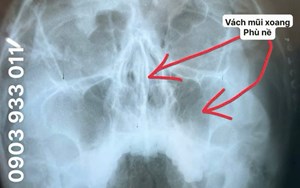

Tư vấn: 0903 933 011 (Ms.Điểu)/ 0934 117 009 (Mr. Nhung)

Hotline: 0903 933 011 - 028.3815.1615